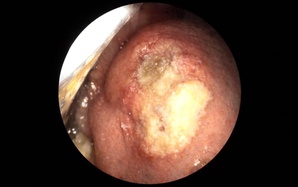

Người phụ nữ ợ hơi, tức ngực đến bệnh viện phát hiện điều bất ngờ

(NLĐO) - Bị ợ hơi sau ăn rồi tức ngực cách đây 2 năm, người phụ nữ đi điều trị nhiều nơi nhưng bệnh tình không thuyên giảm.